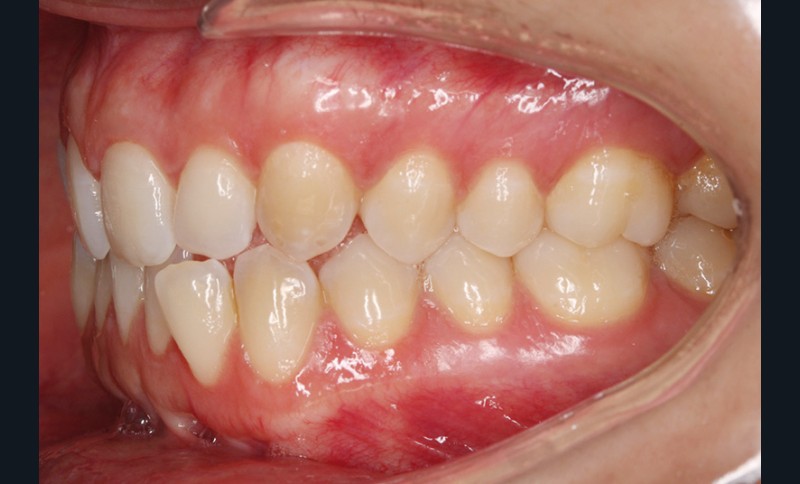

Elle présente une classe I dentaire en denture adulte. Son sourire est perturbé, notamment par la microdontie de son incisive latérale maxillaire droite (la 12). On constate un encombrement modéré au maxillaire (bimarginotopie mésio-palatine et disto-vestibulaire de 13) et plus marqué à la mandibule (monomarginotopie mésio-vestibulaire de 32 et de 43) (fig. 1-6).

Les milieux inter-incisifs ne sont pas coordonnés, à torts partagés, avec une légère déviation à droite du milieu inter-incisif maxillaire et une déviation plus marquée à gauche du milieu inter-incisif mandibulaire ainsi que du point menton. 32 et 33 présentent une tendance à l’exoclusion.